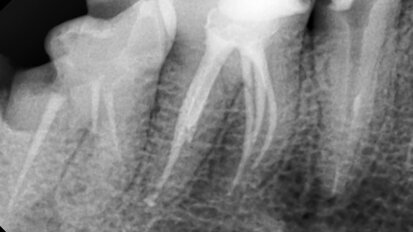

Nový úsměv za jeden den

Čt. 28. května 2020